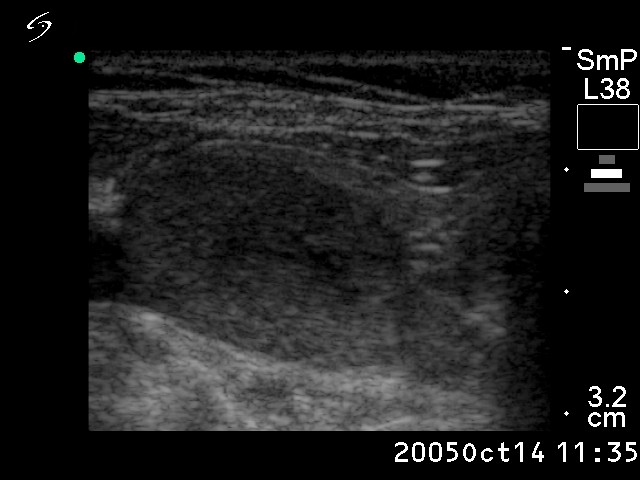

Ultrasonography: the thyroids were echonormal. There was a solitary nodule in the right lobe. A halo sign was not seen, but perinodular blood flow was present. The dimensions of the nodule were 25x16x27 mm.